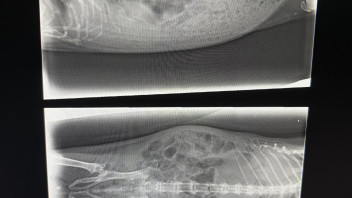

Ich hänge mal ein Bild an mit den Vergleichswerten. So wie ich es interpretiere ist auf jeden Fall ordentlich Blut im Urin. Sehn kann man davon nichts aber es ist quasi instant dunkelgrün geworden als ich draufgetropft habe.

Würde das nicht jetzt eher wieder für eine Entzündung sprechen? Was mich wieder zurückführt zur Frage, müssten die Antibiotika dann nicht geholfen haben? Ich bin grad echt ein bisschen überfordert 😅 aber so lernt man hoffentlich dazu 😊